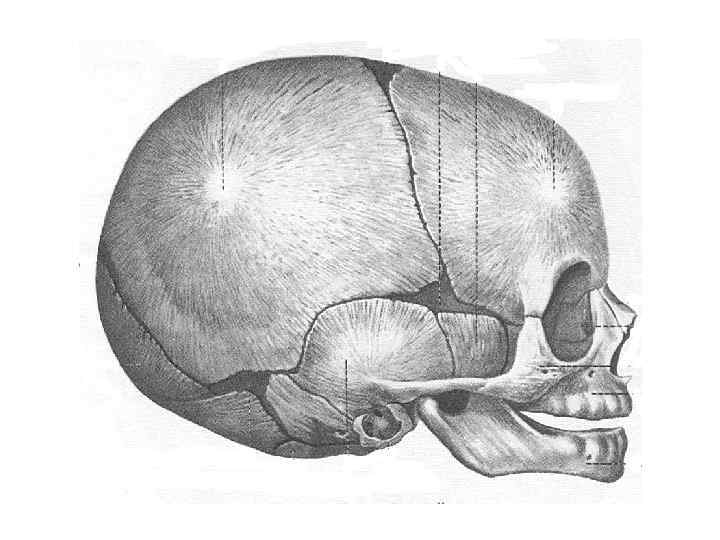

Череп (cranium)

Череп (cranium)

Череп (cranium)

Череп (cranium)

Череп (cranium)

Череп (cranium)

Череп (cranium)

Череп (cranium)

Череп (cranium)

Череп (cranium)

Череп (cranium)

Череп (cranium)